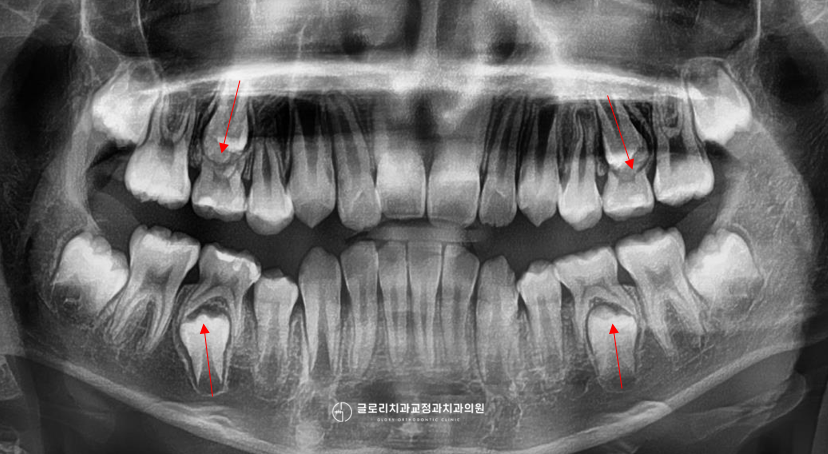

혼합치열기(유치와 영구치가 섞인 시기)에 맞춤 설계된 투명교정 장치로 치열 배열뿐만 아니라 영구치 맹출 공간 확보도 함께 유도할 수 있습니다.

그리고 일반 인비절라인과의 차이점은 아직 나지 않은 영구치 공간까지 미리 예측하여 설계한다는 점입니다.